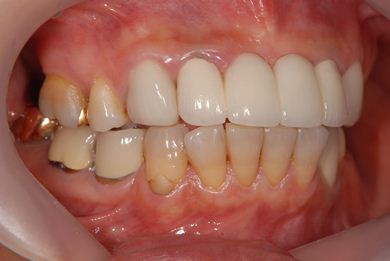

治療前

• 治療前